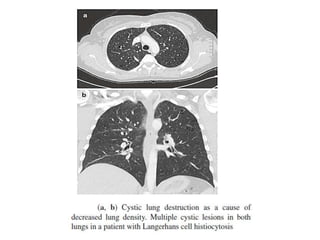

DECREASED

ATTENUATION PATTERN

Generally four causes of decreased lung

attenuation can be found:

• Hypoperfusion

• Air trapping

• Cystic and cyst-like lesions

• Pulmonary emphysema

• Cysts are low-density thin-walled areas that

are well defined and circumscribed and that

have a cellular wall (usually less than 3 mm

thick)

• Most frequent causes of cystic lung changes is

advanced fibrosis giving rise to honeycombing

or honeycomb cysts